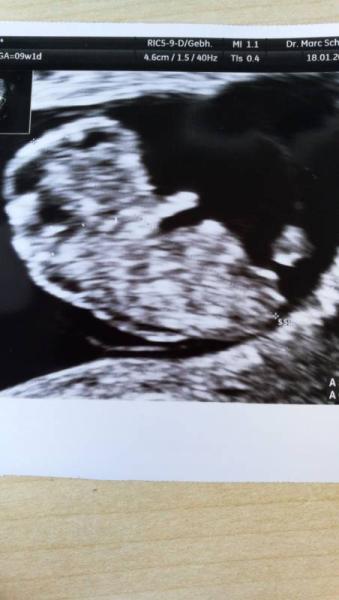

Hallo, Ich hatte ebenfalls zwei FGs letztes Jahr. Seit der 9. SSW waren auch alle Anzeichen weg und ich hab nur geheult, weil es in der Vergangenheit auch so war. ABER: dem Kind geht es gut! Bin wieder in der 10. SSW Auch ich konnte nicht positiv denken, bis zum nächsten Termin. Jetzt habe ich wieder ein wenig Übelkeit. Wann ist dein nächster Termin? Fühl dich gedrückt! Es ist bestimmt alles supi... Genieße es.... Die kommen bestimmt wieder! LG MeioMei86

Bild zu

Tut mir auch Leid für deine FG's aber umso schöner, dass du jetzt in der 10.ssw bist und dein USbild ist echt wunderschön In der 1.SS hatte ich immer ULziehen und Brustschmerzen war dennoch ein Windei. In der 2.SS die gleichen Symptome und es stellte sich heraus, dass es Zwillis ohne waren, verlor sie in der 9.ssw im September. Jetzt kommt mir alles komisch vor, da ich seit dem letzten SST keine Anzeichen habe, stell dir vor hab 10SST gemacht um sicher zu gehen, dass ich Schwanger bin Habe am Dienstag mal HCG messen lassen und war bei 356. US termin habe ich noch nicht ausgemacht, aus Angst...